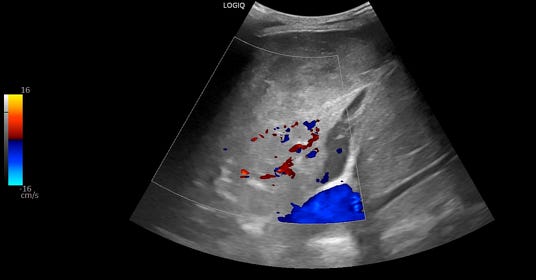

A bedside thoracic ultrasound is also obtained. The right thorax showed:

Ultrasound shows a collapsed right lower lobe with hyperechoic material in the right hemithorax.